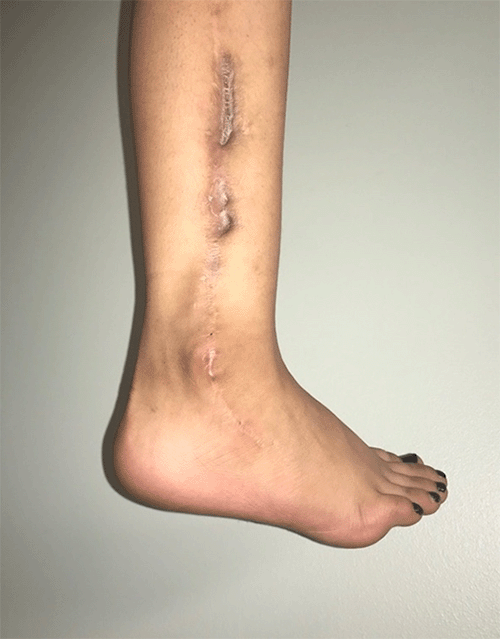

A five-year-old female with no significant past medical history presented with a two-month history of right leg pain without an antecedent traumatic event. On exam, she had a mass over the lateral malleolus on the right. MRI was obtained, which demonstrated a destructive bone lesion measuring 3 × 2 × 14 cm of the distal fibula. She underwent neoadjuvant chemotherapy after a bone biopsy revealed an Ewing sarcoma. Following chemotherapy, her sarcoma was reimaged and found to have decreased in size to 2 × 1 × 11 cm. She was subsequently taken to the operating room and underwent resection of her sarcoma, followed by ipsilateral free vascular transfer of the proximal fibula and epiphyseal plate using the peroneal artery as a pedicle. She is currently 33 months postoperative and is weight-bearing as tolerated to the right lower extremity. She has minimal pain or deformity of the ankle. She has minor hindfoot varus and dynamic supination with gait. She is ambulating independently and is using a lateral heel post to assist with foot position (Figure 1). MRI and plain radiographs were taken at 33 months postoperatively and demonstrated the stable position of the graft with evidence of physeal/epiphyseal remodeling (Figure 2).

Figure 1. Postoperative Photo of Wound. Published With Permission